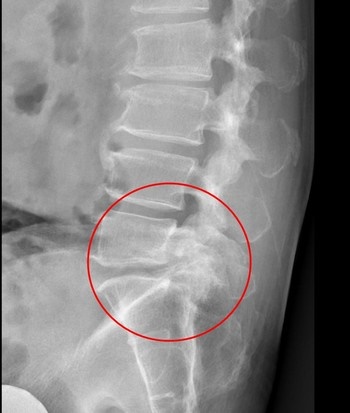

影像檢查顯示,張先生的第五節腰椎椎弓骨折合併脊椎解離。洪祥益主任表示,這類病人多半表現為腰痠背痛、久坐久站困難,通常可先藥物治療觀察,但相較於其他類似問題的病人,張先生疼痛異常明顯,手術中發現脊椎關節內長滿痛風石,這些痛風石如白色黏稠物般,附著在神經與關節縫隙間,若不清乾淨,就會持續引發神經發炎與疼痛,甚至比坐骨神經痛更強烈。團隊透過顯微鏡,在不傷及神經的情況下,仔細將痛風石刮除清理,再以微創固定融合手術完成治療。

左圖:影像檢查顯示,張先生的第五節腰椎椎弓骨折合併脊椎解離。